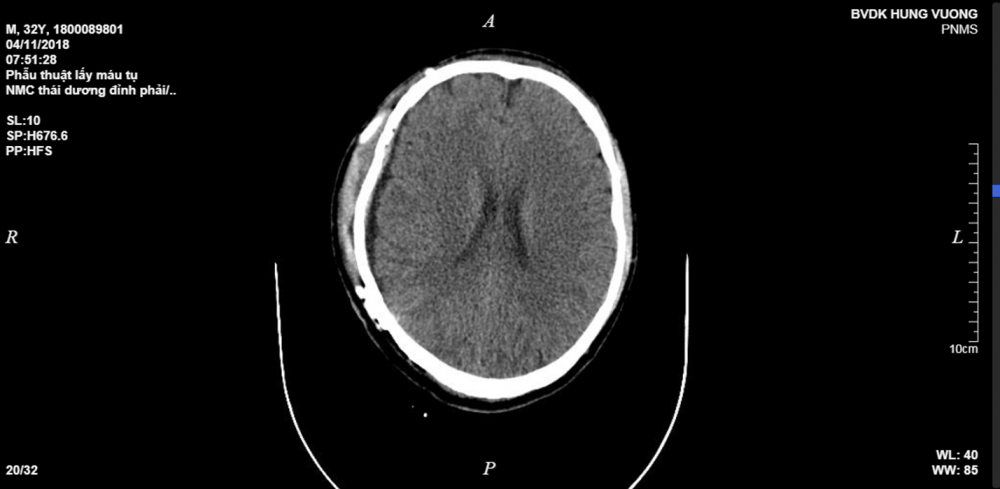

Khi được đưa tới Bệnh viện Đa khoa Hùng Vương cấp cứu, các bác sĩ cho anh P. chụp CT sọ não và thấy hình ảnh tụ máu não ngoài màng cứng vùng thái dương đỉnh phải, vỡ xương đỉnh phải và vỡ xương thái dương, tình trạng rất nguy kịch.

Hình ảnh sọ não bệnh nhân P. sau khi được phẫu thuật. (Ảnh: Bệnh viện cung cấp)